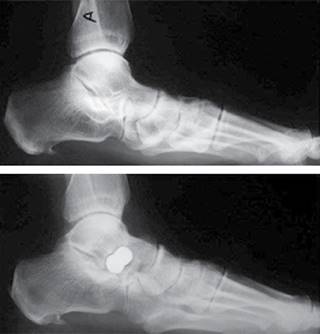

Otra técnica muy utilizada es la tenosinovectomía indicada en pacientes sintomáticos, cuya clínica sea compatible con patología del tendón y la resonancia muestre tendón íntegro con proceso inflamatorio (Figura 2). Este procedimiento tiene indicación como técnica asociada no como técnica aislada y ha evolucionado hacia la tenoscopía49 que permite realizar exploración y desbridamiento del tendón a través de pequeñas incisiones, cosméticamente mejor aceptadas, con menos dolor, menores complicaciones y no requiere inmovilización prolongada, pero con la desventaja de que dificulta la completa visualización del tendón. Sin embargo, tampoco trata la patología mecánica, por lo que se ha empleado asociada a otros procedimientos quirúrgicos de mayor rango como la artrorrisis subastragalina, procedimiento que se expondrá a continuación.48),(52),(53),(54 (Ver apartado de Artrorrisis).

A continuación, se pone el implante definitivo de la endortesis en el seno del tarso (Figura 5). Posteriormente se procede al cierre de la herida y se coloca un vendaje de yeso almohadillado.

Posteriormente se revisa la herida operatoria, se retiran los puntos y se prescribe una bota tipo Walker que el paciente deberá llevar durante un mes, permitiendo la carga. Una vez retirada la bota se indican unas plantillas ortopédicas como medida de protección durante seis meses (Figura 6).

Figura 6: Disfunción del tibial posterior E-II. Endortesis Kalix. Observar la corrección de la línea de Feiss.